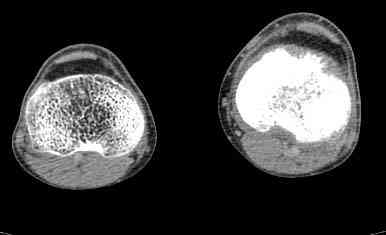

При обращении к нам произведена сцинтиграфия скелета - зоны гиперфиксации РФП: верхняя треть голени- 960%, нижняя треть бедра - 380%, Дистальный метафиз голени и затылочная область - 140%. В легких - метастазов нет. Произведена КТ (картинки в приложении). Учитывая абсолютную нестыковку рентгенологических и морфологических данных повторно биопсия. Выявлено, что первичная биопсия выполнялась из поверхностной параоссальной зоны - там локализованы хрящеподобные массы, далее очень плотная кость без хрящевых участков - биоптат взят фрезой с большим трудом. Морфологического заключения пока нет. Хотелось бы узнать Ваши варианты диагноза и соответственно тактику.